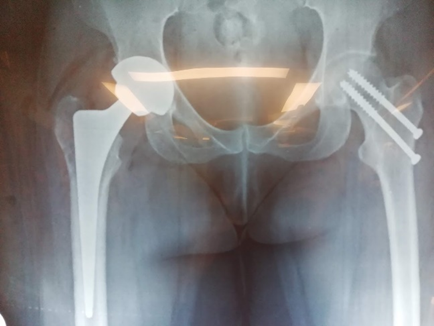

Γυναίκα 45 ετών με αμφοτερόπλευρη αναπτυξιακή δυσπλασία (ΣΕΙ)